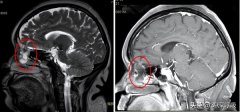

• 脑子出现缺口?40多岁女子一直流鼻涕

脑脊液 鼻漏 肖女士 2025/02/10